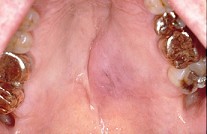

2.下列关于黏液表皮样癌(如图)的叙述,不正确的是  (    )

正确答案:D